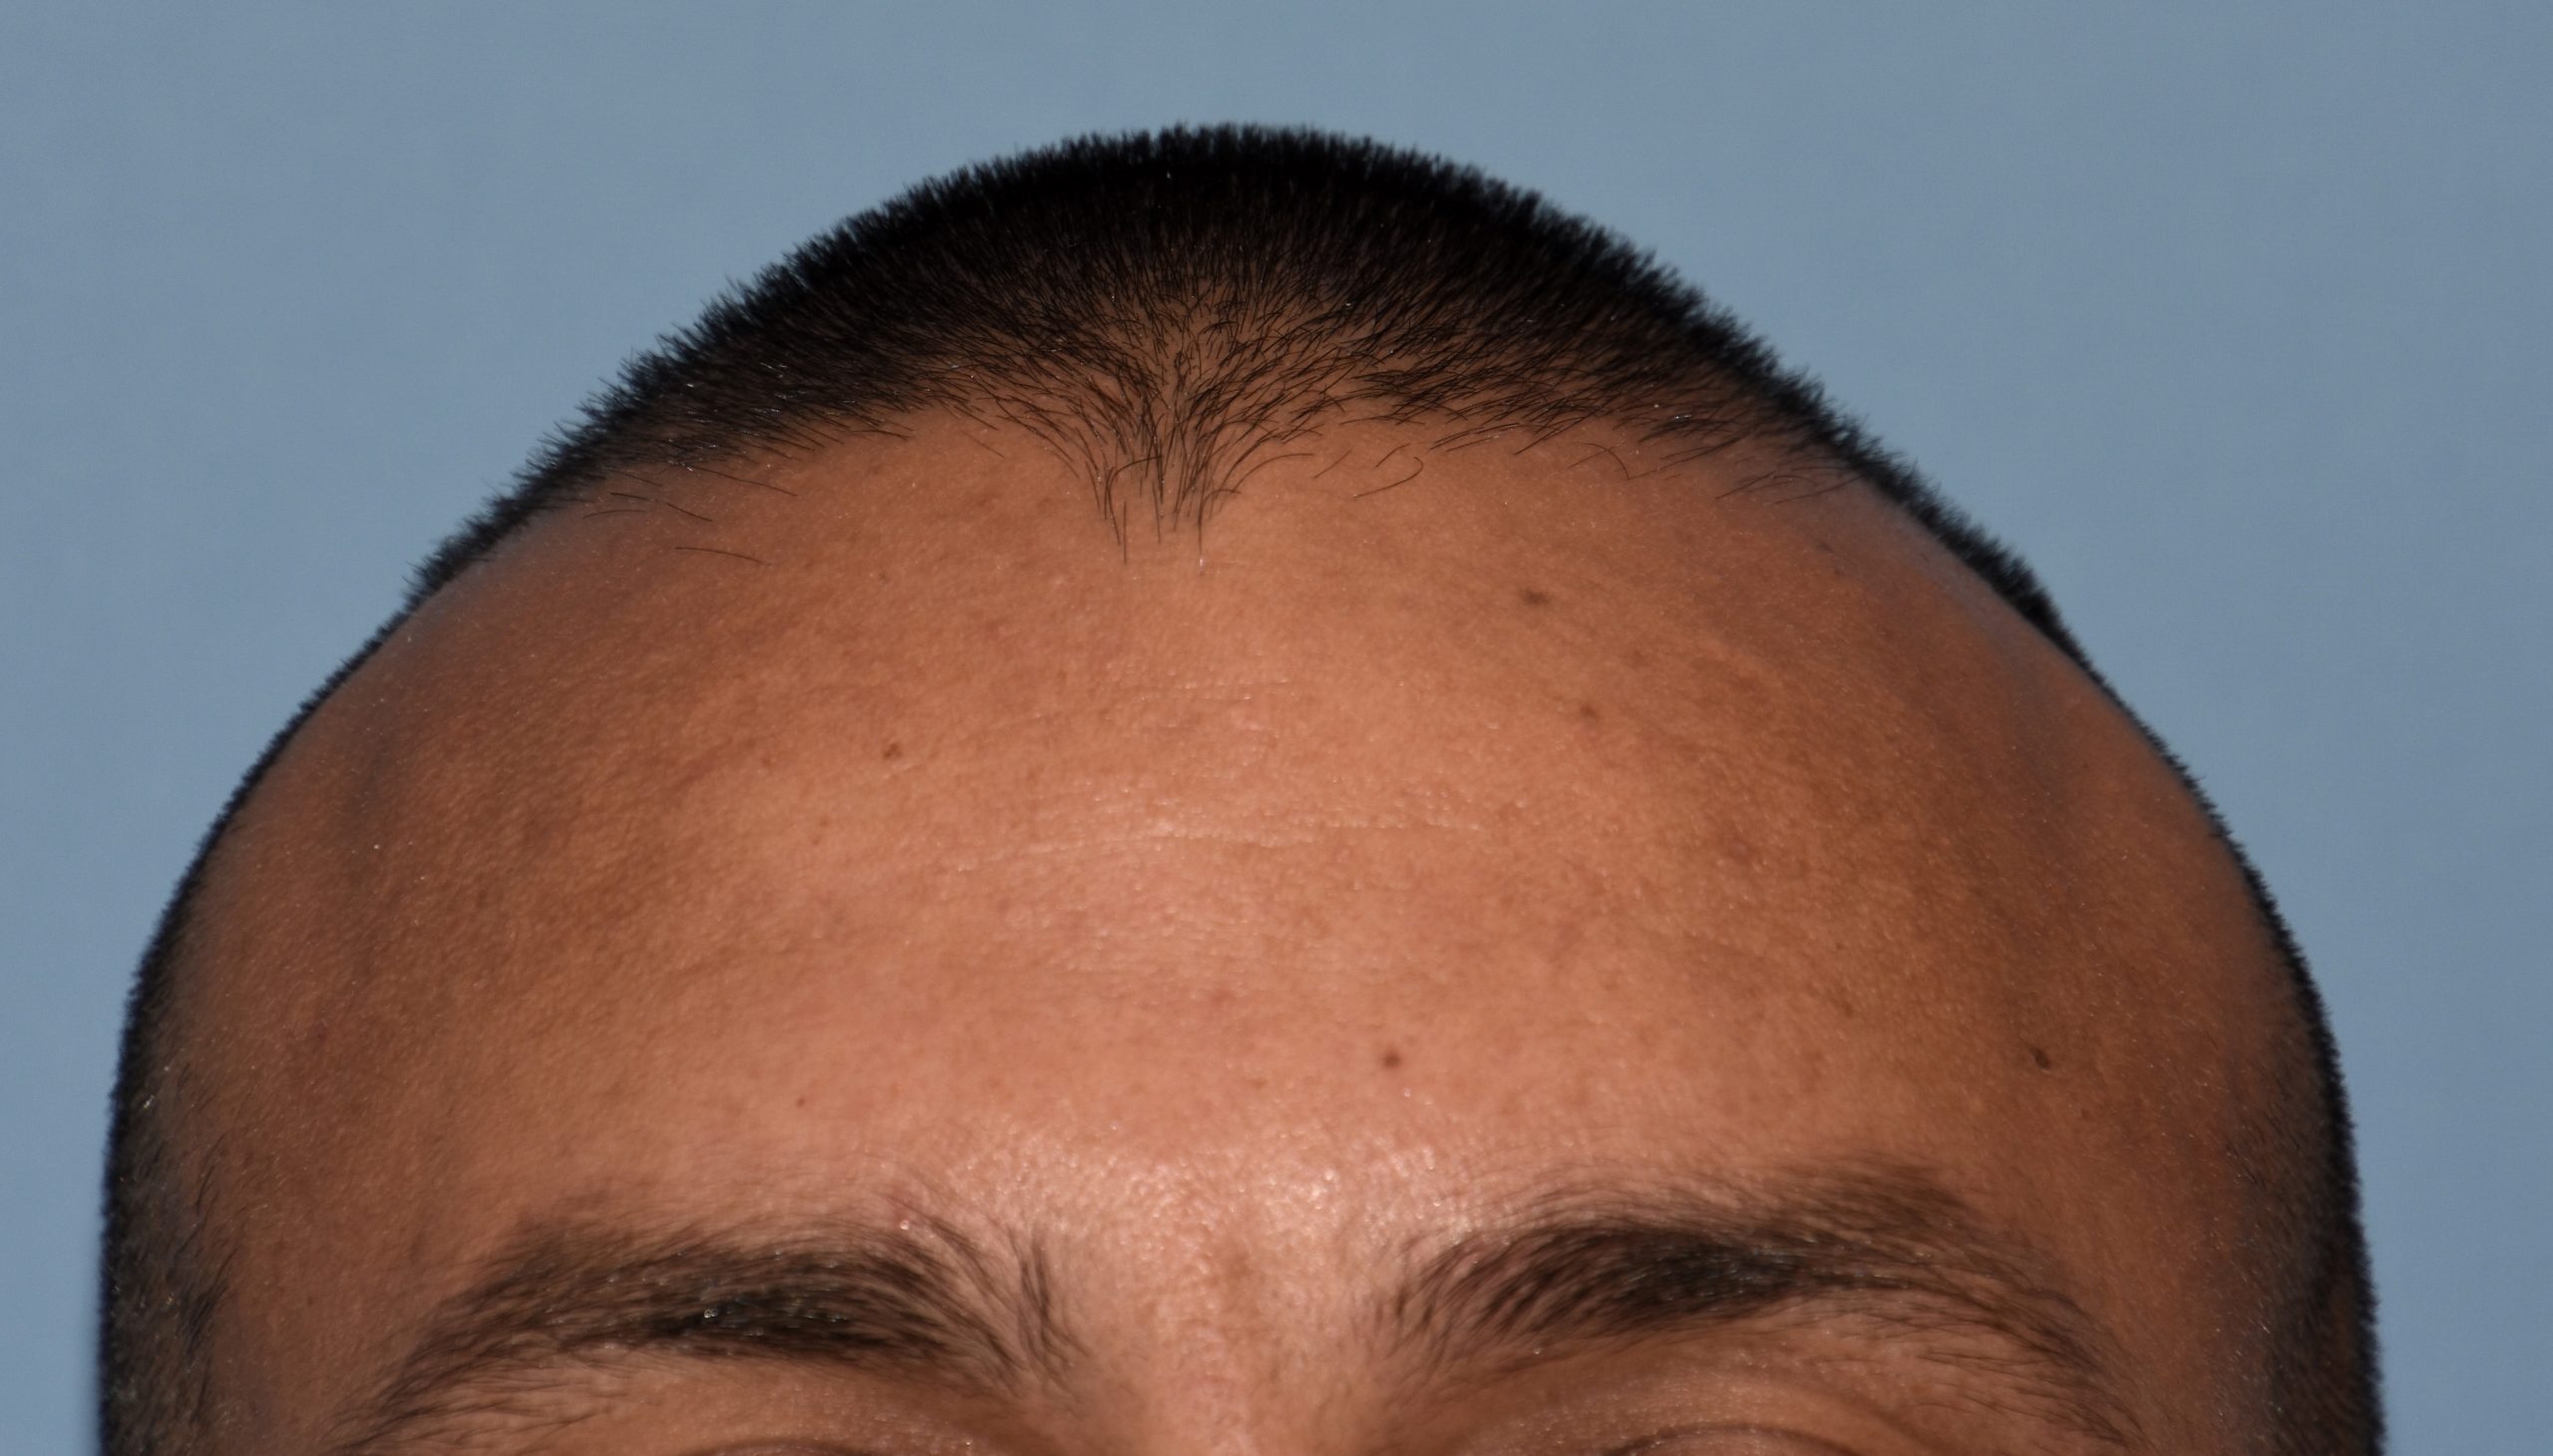

57

Scalp avulsion due to traumatic injury which left a large patch of non-hair bearing scalp.

Hair bearing scalp reconstruction using a first stage tissue expanders and second stage scalp scar removal.

Scalp avulsion due to traumatic injury which left a large patch of non-hair bearing scalp.

Hair bearing scalp reconstruction using a first stage tissue expanders and second stage scalp scar removal.